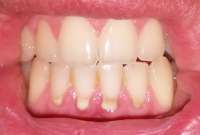

Как и обещал. Забавно, в зеркале кажется не так криво.

Боль на третий день похожа на второй день, спасаюсь болеутоляющим. Но целом уже привык.

Вчера делал панорамный снимок. Всё как >>513480 сказал, ортодонт взял его только посмотреть. Внимание, вопрос знатокам, ортодонт посмотрел на второй пикрелейтед и сказал, что зуб в котором штифт нужно переделывать - канал не полностью залечили, а так же второй зуб - там тоже проблема с каналом и что если ставить брекеты, то им обоим придет пизда. Когда это лечить не понятно, времени в обрез, завтра пойду к своему врачу который год-полтора назад мне эти зубы лечил, послушаю что скажет. В то, что она плохо сделала не хочется верить, но нужно быть реалистом.

Еще вопрос, сегодня пидорю зубы и вижу ДЫРУ, ЧЕРТОВУ ДЫРУ В ДЕСНЕ около места, из которого мне выпилили зуб мудрости. Еще вчера этой дырки не было, засунул туда ершик, дырка оказалась глубокая, вытащил оттуда петрушку, попутно отложив немало так кирпичей. Завтра побегу к хирургу. Всё это уже знатно так заебало, за лето потратил на брекеты, пломбы, снимки, лекарства и прочие операции больше 40к и конца этому не видно.